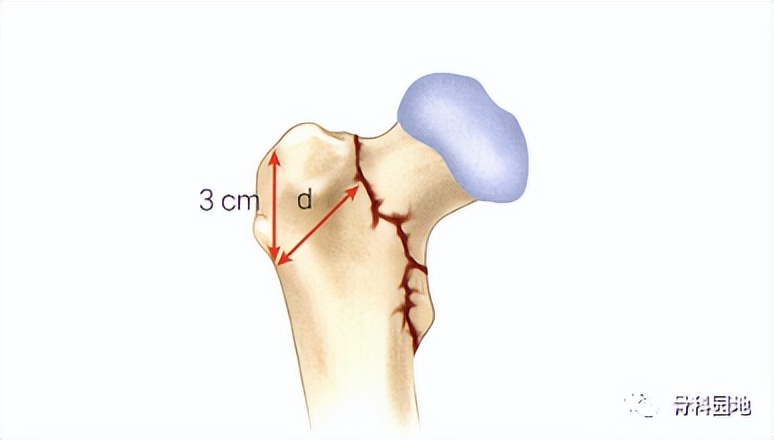

“不稳定”股骨粗隆间骨折的最佳治疗方法仍存在争议。最近的文献表明,AO/OTA的A2骨折由于明显的后内侧粉碎,可以用髓外或髓内装置治疗,但成功率不确定。相比之下,A3型骨折伴侧壁骨折延伸需要髓内固定。多项研究表明,髓外植入物成功治疗转子间骨折需要一个完整的外侧壁。Hsu等人证实,侧壁厚度小于20.5 mm是术后侧壁骨折的可靠预测指标。最新的第14版坎贝尔骨科手术学也明确写道:对于不稳定型股骨转子间骨折(A3骨折和一些A2骨折),最佳治疗方式是使用髓内钉固定。(p2635)

注:外侧壁厚度示意图。在X线正位片上大转子无名结节下方3cm处作为参考点,然后与股骨干成135°角做一条直线,参考点到骨折线的距离即为外侧壁厚度(以毫米为单位)